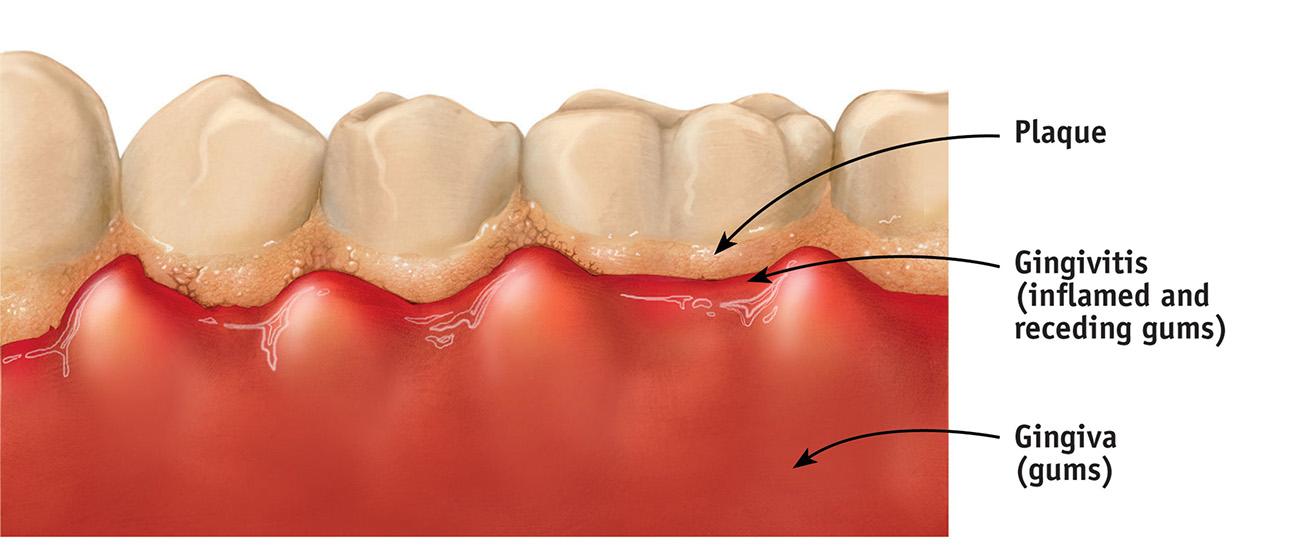

Ignoring the gumline image 1 Ignoring the gumline image 2

The gumline is the area where plaque and bacteria accumulate the most, and it’s the #1 place people miss. If plaque stays here too long, it leads to:

• Gingivitis

• Bleeding gums

• Bad breath

• Early periodontal disease

Correct technique: Hold your toothbrush at a 45° angle toward the gums and gently sweep:

• Downward for upper teeth

• Upward for lower teeth

Use small circular motions to disrupt plaque. You’re not just brushing the teeth — you’re brushing the junction between the teeth and gums.